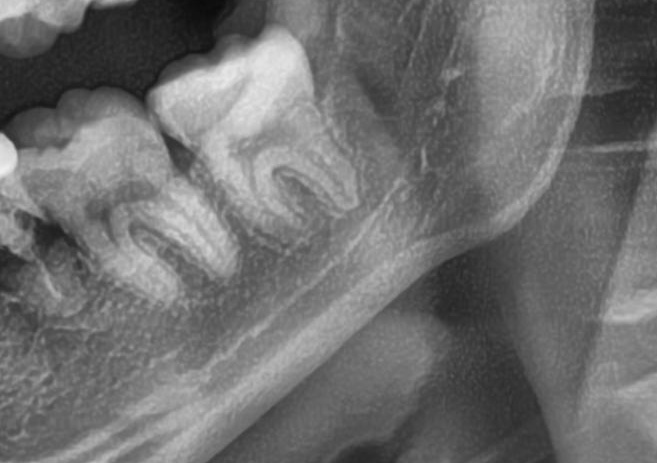

次にパノラマ写真を撮影してみると、左下の親知らずは手前の歯と並んでまっすぐに生えているのが確認できました。

さらに、下顎の親知らずは下歯槽神経に非常に近いところに生えている場合もあるため、CTも撮影し詳しい解析を行います。

親知らずの根っこは下歯槽神経から近い距離にありますが、抜歯は可能との診断でした。